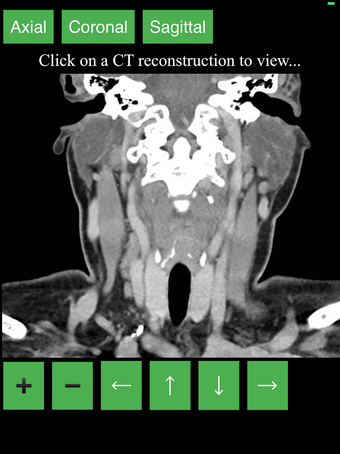

Aplikacja wyświetla przekrojowy obraz tomograficzny ciała człowieka i używa systemu kodowania kolorów, aby łatwo identyfikować różne struktury tkanek miękkich i kości. Może również być używana do badania określonej części ciała, takiej jak szyja, czaszka, obręcz barkowa lub klatka piersiowa.

Użytkownik może przesuwać obraz i powiększać go, aby lepiej zidentyfikować struktury i powiększyć obraz do dalszych badań.